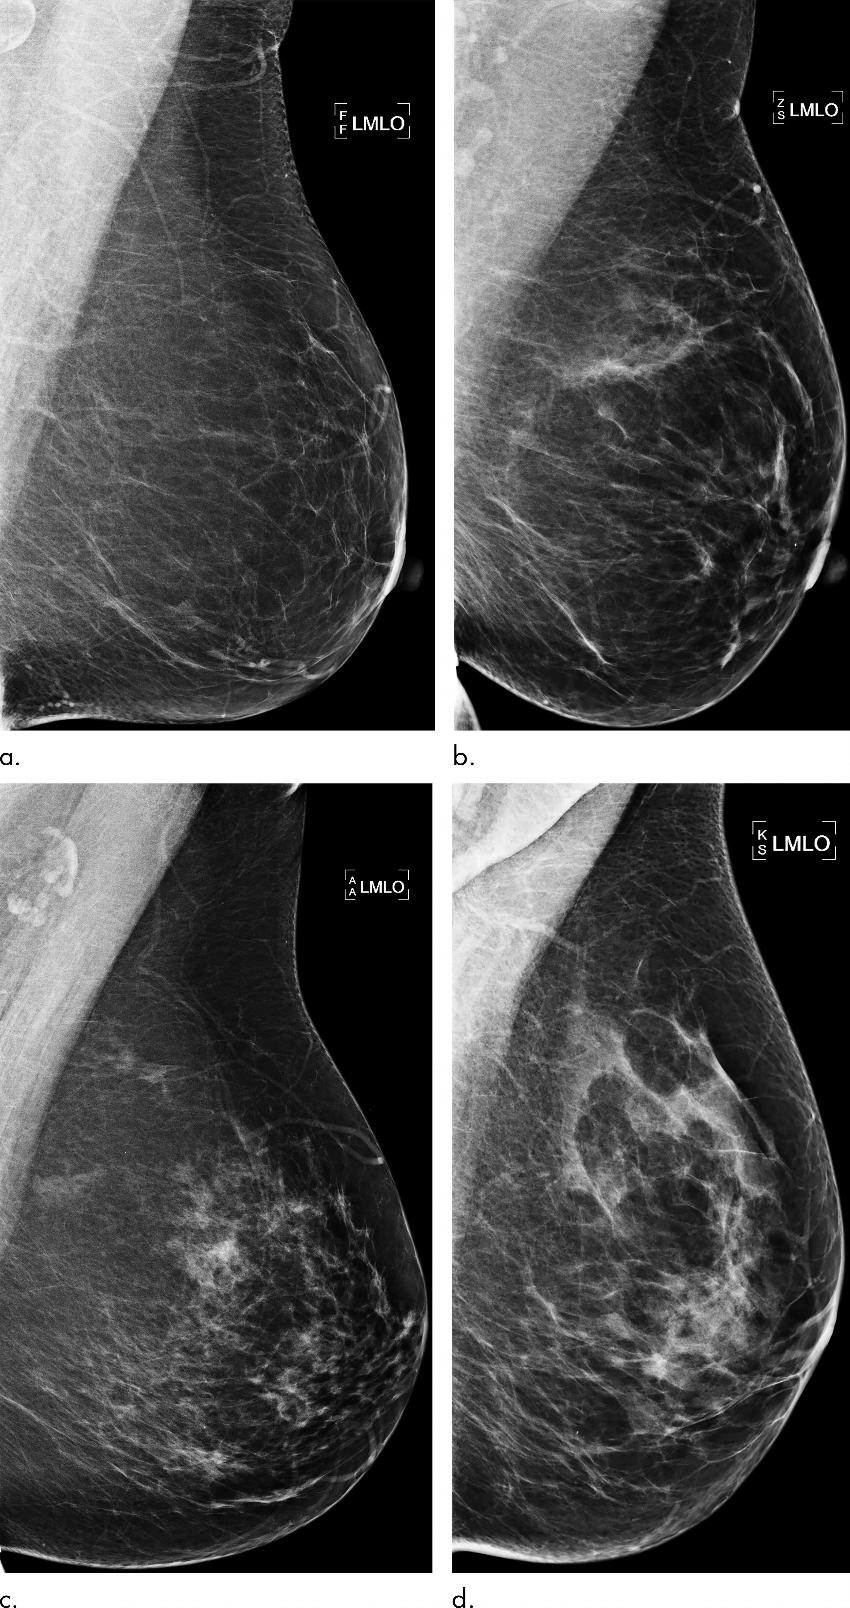

Figure 2. Examples of mammograms with concordance between deep learning (DL) risk score and outcome of breast cancer (true predictions). All images are mediolateral oblique views of left breast. (a) Mammogram in 55-year-old woman with low DL risk score (0.05) who was not diagnosed with breast cancer (ie, true-negative prediction). (b) Mammogram in 47-year-old woman with low DL risk score (0.06) who was not diagnosed with breast cancer (ie, true-negative prediction). (c) Mammogram in 56-year-old woman with high DL risk score (0.30) who received a diagnosis of breast cancer 5.1 years after the examination (ie, true-positive prediction). (d) Mammogram in 57-year-old woman with high DL risk score (0.30) who received a diagnosis of breast cancer 5.0 years after the examination (ie, true-positive prediction). LMLO = left mediolateral oblique.

High-res (TIF) version